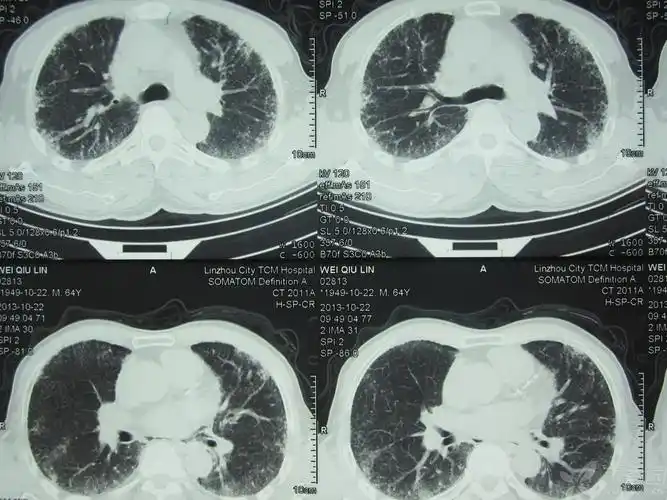

【病例会诊】肺部ct 请各位专家帮忙看看 患者咳嗽4个月痰少 难于诊断